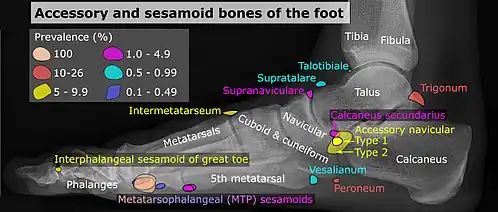

Pied

| Os | Prévalence [9] |

|---|---|

| Os sésamoïdes | |

| Sésamoïdes au niveau de l'articulation articulation métatarso-phalangienne de l'hallux | Toujours présente |

| Sésamoïde du deuxième métatarsien | 0,4% |

| Sésamoïde du troisième métatarsien | 0,2% |

| Sésamoïde du quatrième métatarsien | 0,1% |

| Sésamoïdes du cinquième métatarsien | 4,3% |

| Sésamoïde de l'articulation interphalangienne de l'hallux | 2 à 13 % |

| Os non sésamoïdes | |

| Os trigone (non visible dans la projection dorso-plantaire) | 7 à 25 % |

| Os peroneum | Jusqu'à 26% |

| Os naviculaire accessoire | 2 à 21 % |

| Os intermetatarseum | 1 à 13 % |

| Os supranaviculare | 1,0 à 3,5 % |

| Os calcanéus secondaire | 0,6 à 7 % |

| Os supratalare | 0,2 à 2,4 % |

| Os vésalianum | 0,1 à 1 % |

| Os talotibiale | 0,5% |

Un os naviculaire accessoire se développe parfois devant la cheville vers l'intérieur du pied. Cet os peut être présent chez environ 2 à 21 % de la population générale et est généralement asymptomatique[10],[11],[12]. Lorsqu’il est symptomatique, une intervention chirurgicale peut être nécessaire.

La classification Geist divise les os naviculaires accessoires en trois types[12] :

- Type 1 : os sésamoïde de 2 à 3 mmm dans le tendon distal du muscle tibial postérieur, généralement asymptomatique,

- Type 2 : osselet triangulaire ou en forme de cœur mesurant jusqu'à 12 mm, qui représente un centre d'ossification secondaire relié à la tubérosité naviculaire par un connecteur 1–2 mm de fibrocartilage ou de cartilage hyalin, des parties du tendon du muscle tibial postérieur s'insèrent parfois sur l'osselet accessoire, ce qui peut provoquer un dysfonctionnement et donc des symptômes,

- Type 3 : Un os corné présentant une tubérosité naviculaire médiale élargie, parfois symptomatique en raison de la formation d’oignons.

Os trigone

L'os trigone (ou astragale surnuméraire ou astragale accessoire) provient de l'échec de la fusion du tubercule latéral du processus postérieur du talus . On estime qu'il est présent chez 7 à 25 % des adultes[9].